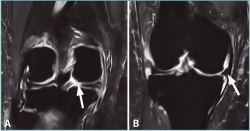

Además, este plano es óptimo para la valoración de la extrusión meniscal o desplazamiento del menisco sobre el borde del platillo tibial, la cual es significativa cuando es superior a 3 mm del menisco sobre el borde tibial(59)(Figura 7). Dicha extrusión, si bien puede aparecer en las roturas horizontales, es de menor entidad en comparación con los desgarros radiales, en especial con las roturas completas, siendo más frecuente en la afectación del menisco medial(59). Esto último es debido a que el menisco lateral se encuentra estabilizado por los LMF, por lo que para que aparezca una extrusión del mismo es necesaria una rotura asociada de dichos ligamentos.

Figura 7. Imágenes coronales de resonancia magnética de una rodilla con rotura de la raíz posterior del menisco medial. A: corte a nivel del cuerno posterior, donde se aprecia la rotura (flecha); B: corte a nivel del cuerpo del menisco, donde puede apreciarse la extrusión del mismo (flecha).